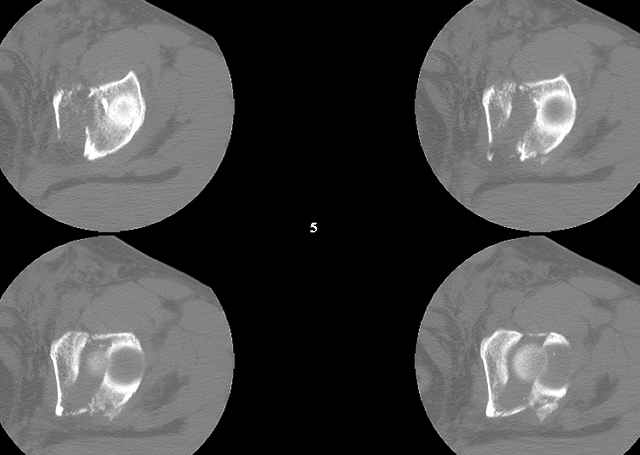

You can adjust the quadrilateral surface contact point as needed to get the fracture to reduce...we plan this based on the fracture orientation on the preop CT scan images...the clamp should be balanced to avoid over compressing one portion and distracting the other limb. Go back to and you¹ll see on the injury CT where the clamp tines need to be.

Prone

Here's a pic from the foot of the bed and you can see the clamp in the wound and the knee is extended so he must've had a tight rectus. The C-arm is rolled back to an obturator oblique image to reveal the anterior column...we put a slight outlet tilt to combine the images and give a better view of the anterior column...we can see the posterior column limb reduction in the wound, we can palpate the quadrilateral surface limb, and the image demonstrates the anterior column portion...you can adjust the tilt and rotation to image tangentially to the fracture plane if you'd like. We've inserted a 2mm K wire to site the starting point and aim/orientation for the drill and screw

Prone Imaging

same image, just another look.

Prone Inlet

OK, now we're inserting the drill percutaneosuy using a sleeve. This fluoro shot is not for this patient (notice no clamp) but I was too lazy to go searching the PACS for one with the clamp on, so pretend...I'll save the next ones and send along...the imaging is the same and the clamp doesn't obstruct imaging other than very rarely...you can always tilt the C-arm a bit to clear it if the clamp obstructs the exact spot that you'd like to see. We'll assume that everyone knows the safe zone for a medullary ramus screw. Use a calibrated drill and sleeve of known length to simplify your life...or use Alex's fancy cannulated screws...I like 3.5mm screws because the oscillating 2.5mm drill bounces and remains intraosseus when it oscillates and contacts endosteal cortical ramus... so will the screw, and like a long bent screw IF the fracture is clamped... if unclamped, when the screw contacts the endosteum, it pushes the reduction apart instead of bouncing. The big 7mm cannulated screws fit few patients and extrude...we very rarely use them any more...you'll see an old one later.